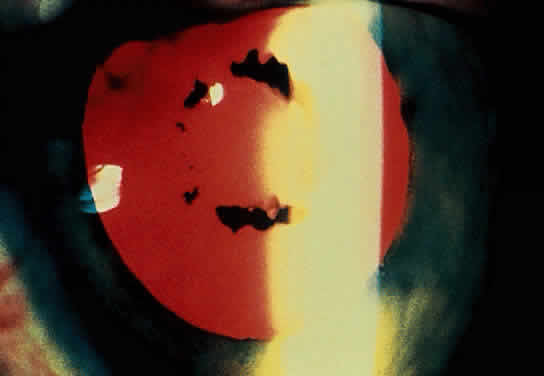

The conjunctivitis is usually described as mucopurulent and may be sterile. It may be accompanied by an iridocyclitis, episcleritis, or scleritis. Punctate and subepithelial corneal involvement has been reported. The iridocyclitis may be the presenting ocular manifestation. Recurrences are usually associated with an acute iridocyclitis, which is of rapid onset with conjunctival and episcleral edema and injection. The corneal endothelium has cellular debris and poorly defined, small-sized to medium-sized keratic precipitates.30 Heavy flare and cells and a very early tendency toward formation of posterior synechiae is characteristic, more so than in most other forms of acute iridocyclitis (Figs. 1, 2, and 3). Even the most aggressive pupil dilation management is sometimes inadequate for preventing synechiae. A peripheral iridectomy may be necessary to prevent iris bombé and angle closure if the synechiae cannot be broken enough to establish an opening for aqueous through the pupil (Fig. 4). The heavy flare is sometimes so plasmoid that cells are immobile and a fibrinlike clot may be seen in the pupil opening as the inflammation resolves. Cells and inflammatory debris may be seen in the vitreous, and blurring of the disc margins and macular edema may occur with severe or prolonged episodes. Lens clouding and posterior subcapsular cataracts occur with prolonged or repeated episodes. Hypotony can occur after a severe or prolonged course and may persist after resolution. Occasionally, secondary glaucoma may occur, owing to the anterior chamber reaction, in which case it will resolve as the inflammation resolves. With repeated recurrences, damage to the trabecular meshwork may occur, and prolonged recalcitrant glaucoma may result that may be poorly responsive to any medical or surgical management. This can be a serious factor in permanent visual loss with this type of iridocyclitis.15,16,30,31

Fig. 4. Complete pupillary synechiae with pupil block requiring peripheral iridectomy in severe iridocyclitis with Reiter's disease.